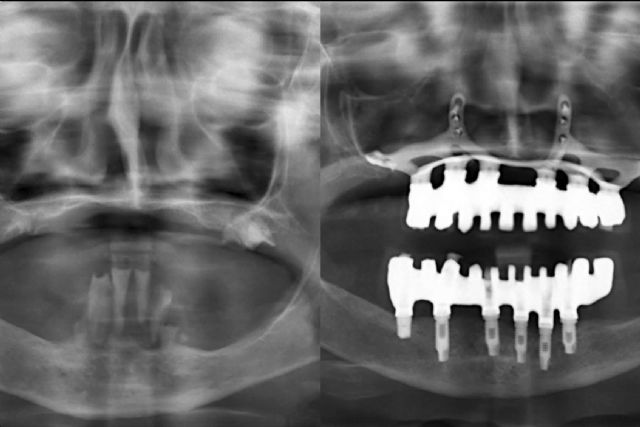

Por otro lado, los cirujanos comenzarán haciéndose una planificación digital y la elección de los materiales regenerativos que mejor se adapten al paciente. Para alcanzar el diagnóstico más preciso, la clínica utiliza tecnología 3D de escáner, con el fin de confeccionar prótesis personalizadas, que pueden ser colocadas en una única intervención.

Concretamente, un implante dental es un tornillo fabricado en titanio que se inserta en el hueso maxilar con el fin de sustituir a la raíz del diente que falta.

En los casos más complejos en los que falta la cantidad de hueso ideal, la técnica del injerto óseo es la indicada, al colocar tejido autólogo, tomado del propio paciente; o heterólogo, de otra especie, por lo general la bovina, para contar con un buen soporte del implante, sin rechazo ni reacciones alérgicas. Sin embargo, otros procedimientos que ofrece la clínica son los implantes corticales en caso de atrofia ósea extrema, los implantes cigomáticos y la técnica de elevación de seno maxilar.

Con muchas de estas técnicas se puede recurrir a la carga inmediata, es decir, colocar la prótesis fija pero provisional sobre estos implantes recién colocados.